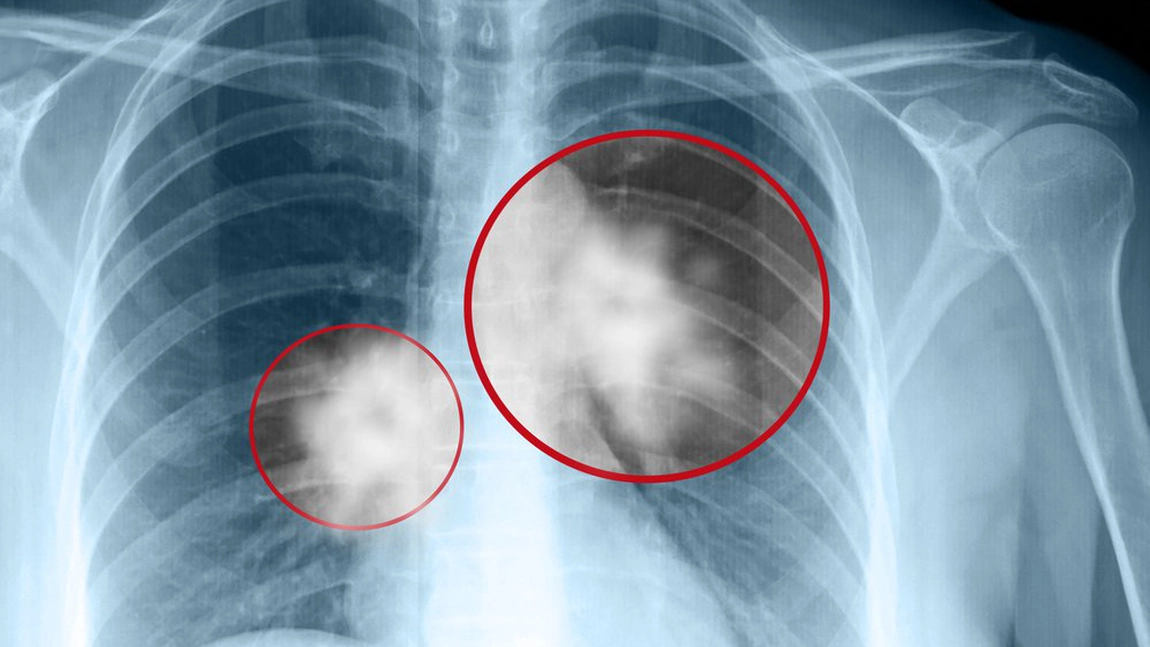

Cancer pulmonar: simptome, persoane cu risc. Uneori, nu sunt detectabile simptome. Cele mai frecvente simptome sunt următoarele:

Cancer pulmonar: simptome, persoane cu risc